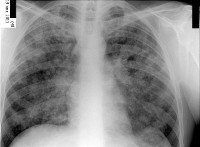

A19 Милиарный туберкулез